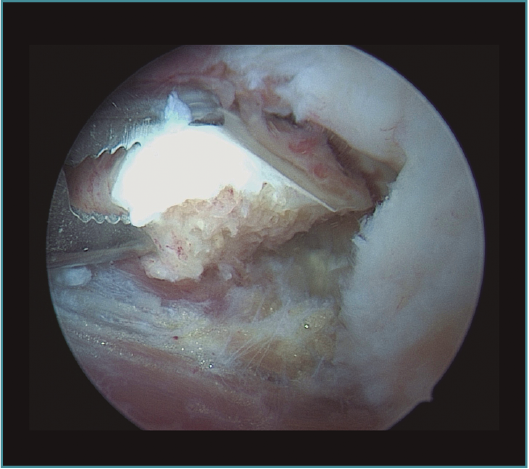

Método: hemos revisado 38 pacientes con codo rígido postraumático o degenerativo que se trataron mediante artrolisis artroscópica entre 2013 y 2016, con un seguimiento medio de 25 meses (38-15). Según la etiología de la rigidez, clasificamos a los pacientes en 2 grupos: grupo 1, los pacientes con rigidez por patología degenerativa del codo, y grupo 2, los pacientes con rigidez postraumática. Clasificamos la rigidez siguiendo la escala de Morrey y utilizamos la escala funcional Mayo Elbow Performance Index (MEPI), que evalúa el dolor, la movilidad, la estabilidad y la función del codo pre- y postoperatoriamente. Describimos los procedimientos artroscópicos realizados en cada paciente, que incluyen la sinovectomía, el desbridamiento de tejido fibroso, la capsulectomía anterior y/o posterior, la resección de osteofitos en la parte anterior y posterior del codo, la extirpación de cuerpos libres y la liberación “abierta” del nervio cubital.

Method: a review was performed on 38 patients with stiff elbow due to degenerative or post-traumatic reasons, and who were treated by arthroscopic arthrolysis between 2013 and 2016, with a mean follow-up of 25 months (38-15). Elbow stiffness was classified following the Morrey scale and the Mayo Elbow Performance Index (MEPI) functional scale was used to evaluate pain, mobility, stability and elbow function pre- and post-operatively. The arthroscopic procedures performed on each patient are described, including synovectomy, debridement of fibrous tissue, anterior and/or posterior capsulotomy, resection of osteophytes in the anterior and posterior part of the elbow, extirpation of loose bodies and open release of the ulnar nerve.